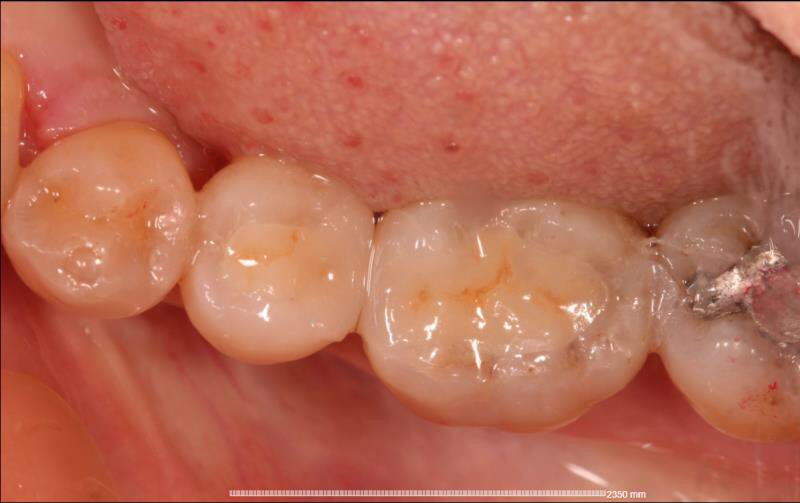

治疗步骤:1 去净龋坏, 2 制备洞形,3 扫描,4 切割制作,5 戴牙。

我院CEREC设备源自德国进口(西诺德公司),扫描出的数字化模型相较于传统取模更精确,且因扫描头较小,舒适性较传统取模更高。

配套的进口切割设备当天即可戴牙,不需要发往加工厂,节省了就诊时间,戴牙后即刻进食。